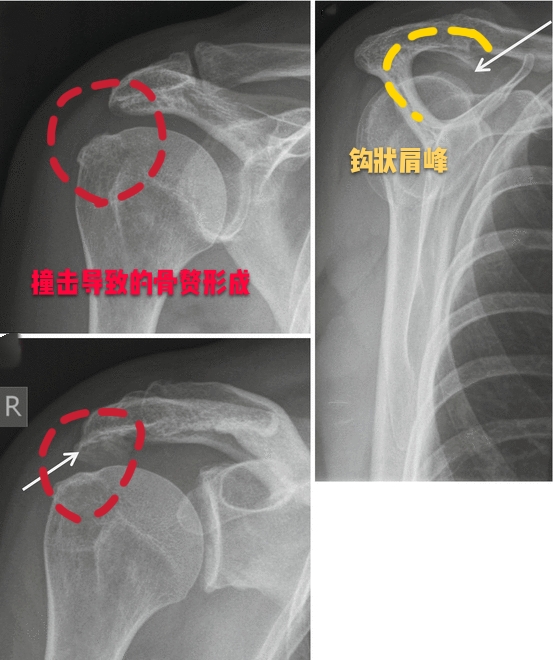

在给大家详细的讲解肩痛之前,大家需要对肩关节的骨骼解剖有一定的认识,我们很多朋友可能知道肩关节的肱骨头、知道肩胛骨,但是很多朋友比较忽视的一个结构就是我们的肩峰,大家在下图可以看到明确的肩峰的位置,其实形象的说,我们可以把肩关节看成是一个小房子,那么肩峰就是房屋的顶棚和房檐儿。

这个房檐形态不是特别的一样,每一个人都有各自的肩峰形态,一般情况下我们的肩峰形态有三种,1种是平的,第2种是略弯曲的,第3种就是钩状的,现在也有人发现有一些人的肩峰是向上翘的,但是这种肩峰不会诱发特殊的症状。主要会导致我们出现肩痛的问题,是三型肩峰,也就是钩状的肩峰,因为向下呈钩状的肩峰,在我们的肩关节活动过程当中,导致肩关节间隙的狭小,会在肩关节活动的过程当中导致撞击!尤其是肩关节做一些前屈、外展、上举的动作时,比如抬起胳膊够比较高的东西,比如羽毛球的挥拍动作。

●肩关节撞击综合征导致的肩痛:肩关节撞击综合症导致的疼痛,往往由固定的动作诱发,疼痛不是特别的明显时,往往不是特别受到重视,有些患者在做特殊动作,比如挥拍动作的时候,会感觉肩关节内有的响声,症状比较明显的时候,会伴有疼痛。

通常情况下进行肩关节的x线检查或者是核磁检查,可以帮助我们明确肩关节是否存在着肩峰形态的异常以及撞击。

但如果患者经过了保守治疗以后症状仍然特别严重,有可能要进行肩关节镜手术治疗,将钩状的肩峰削平,去除撞击的因素,患者的症状也就会消失了。

对于这样来医院比较急的肩痛患者,往往要首先考虑是否存在着钙化性冈上肌腱炎,要首先给予患者进行最简单的肩关节普通x线平片检查,费用比较低,而且出片比较快,要首先判断是否存在肩关节周边的钙化。